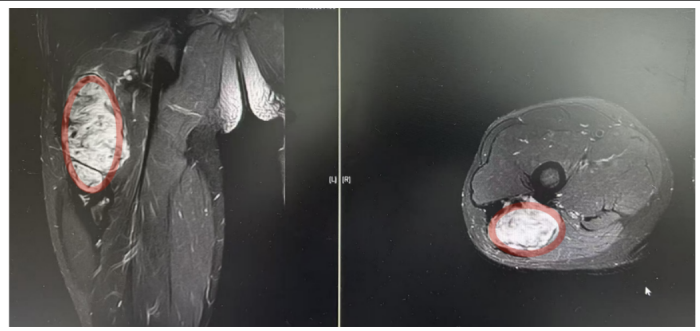

术前影像:红色标记部分为侵袭性纤维瘤

“患者入院后MR检查提示恶性肿瘤可能,肿块约10*2*2CM大小,经B超引导下行穿刺活检,病理提示:侵袭性纤维瘤病。”据手足显微外科副主任医师曾驰介绍,由于肿块较大,无法保守治疗,在完善术前准备后行瘤体切除术,手术顺利,术后患者恢复良好。